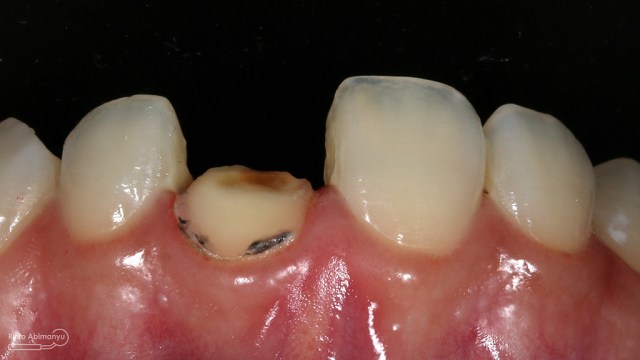

Kasus hari ini tentang gigi-gigi anterior yang fraktur karena kecelakaan lalu lintas. Pasien datang menceritakan kejadian yang dialaminya dan meminta saran bagaimana sebaiknya tindakan yang dilakukan pada giginya…

Begini kondisi klinis saat datang…

Foto klinis gigi-gigi anterior yang mengalami fraktur